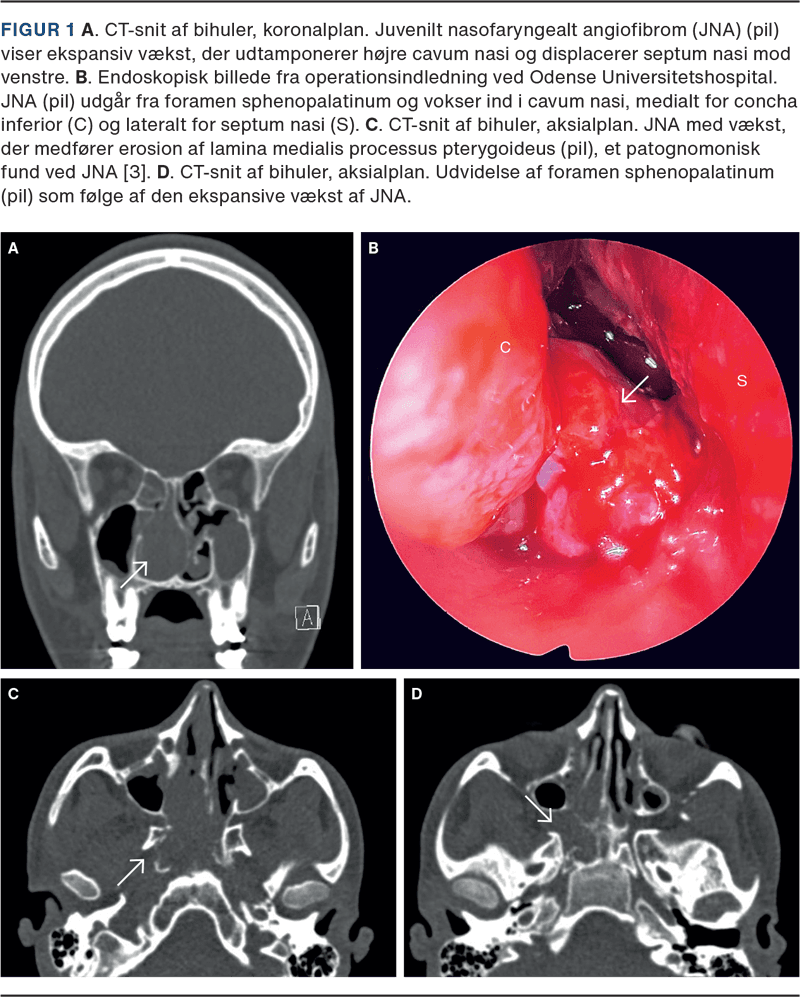

Der blev fundet indikation for bihulekirurgi i fuld narkose på mistanke om en choanalpolyp. Under operation blev der taget biopsier, hvilket resulterede i kraftig blødning, og man afstod fra resektion. Man opnåede hæmostase efter detumescerende tamponade og infusion med tranexamsyre og tamponade med dobbeltballon Rapid Rhino. Den totale blødningsmængde var 1.250 ml. Patienten blev ekstuberet og, på mistanke om JNA, overflyttet til Odense Universitetshospital (OUH) for observation og videre behandling. I stabil fase fik patienten foretaget MR med angiografi og embolisering efterfulgt af endoskopisk resektion af JNA (Figur 1). Det samlede blodtab var her på 700 ml.

Makroskopisk kan JNA beskrives som velafgrænsede, adhærente, karrige tumorer i rødgrå farvenuancer, der kan være affladede eller stilkede [3, 4]. JNA opstår typisk nær foramen sphenopalatinum og kan ekspandere destruktivt ind i næsekavitet, nasofharynx, orbita, paranasale sini og kraniebasis [3]. På grund af vækst og lokalisation er JNA en behandlingsmæssig udfordring med høj blødningsrisiko, hvorfor biopsi frarådes; diagnosen, udbredelsen og karforsyning kan i stedet bekræftes med CT og MR-skanning med angiosekvenser.